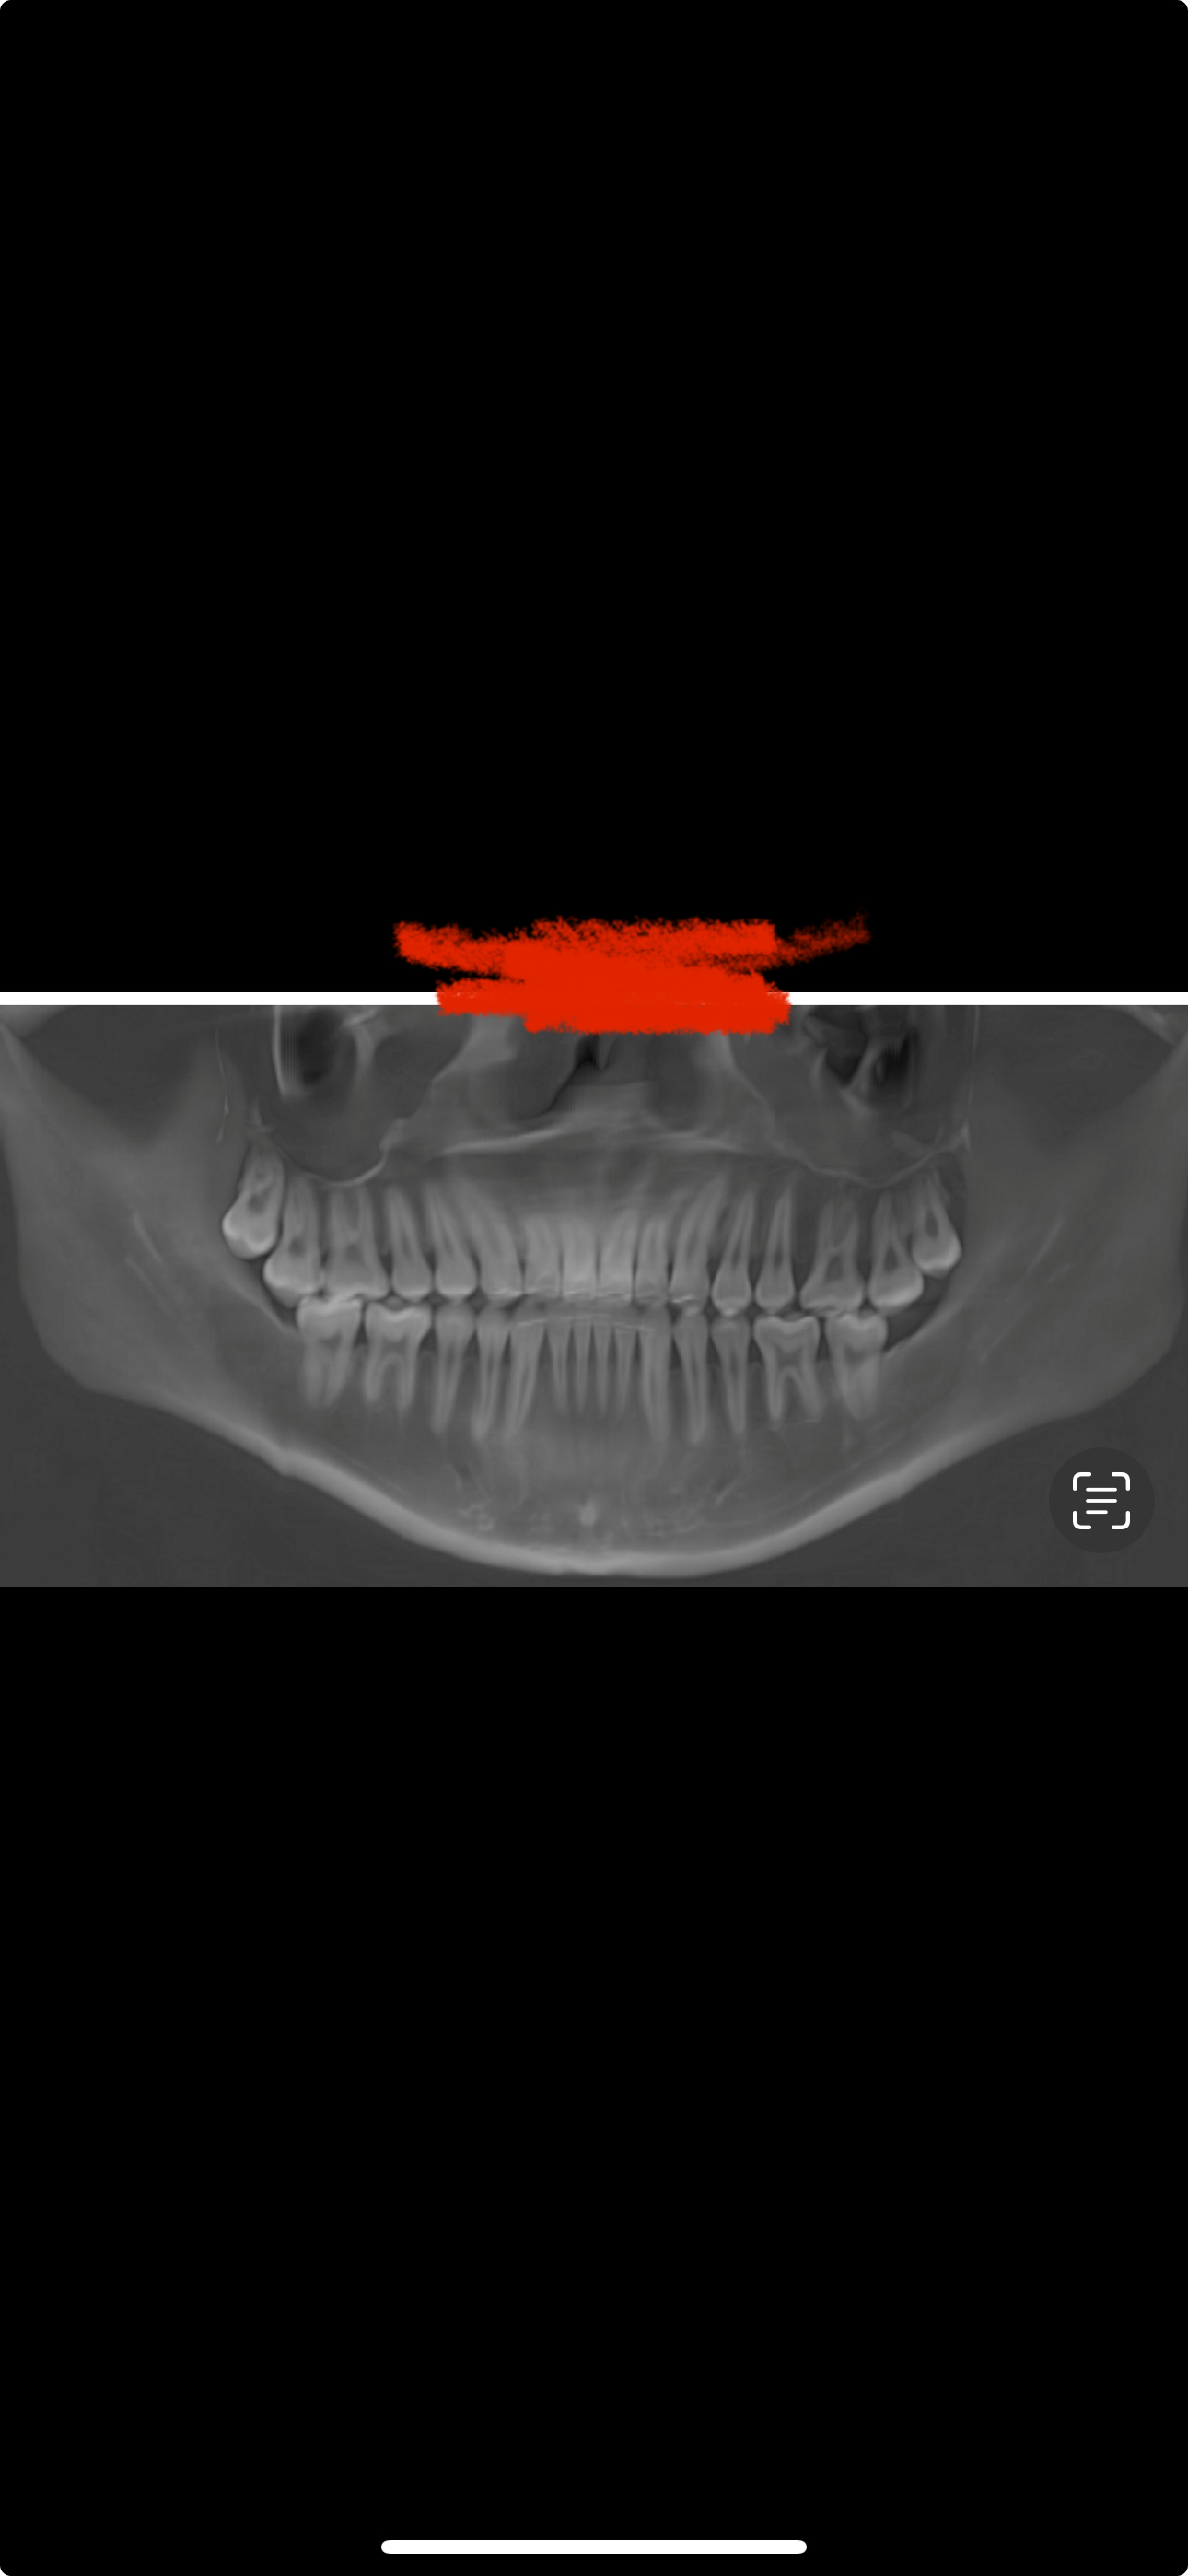

DO I REMOVE MY WISDOM TEETH? alright so basically my ortho said i gotta remove my upper wisdom teeth as i'm doing marpe to create space to decompensate and upright my hella flared incisors (upper front teeth). i've already removed my bottom wisdom teeth, i had to as one of them were growing in sideways. and i'm also doing a beneslider with the marpe for distillation to pull my upper molars backwards to allow for decompensation of my flared incisors. is there any way to keep my upper teeth and should i remove them as my ortho said without removing them ill limit how far the molars can be pulled back with the beneslider as the wisdom teeth are in the way, as well as when they grow in they'll be biting on my gums just causing a bunch of issues down the line. i've attached an xray of my teeth but my upper wisdoms are impacted. what should i do?